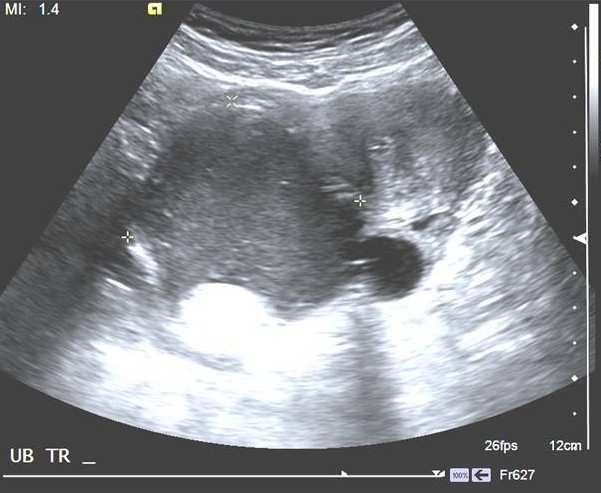

37歲孕婦,G1P0,妊娠36週,血壓180/110 mmHg,接受下列超音波檢查,如圖所示。則該檢查是:

詳解

登入後即可查看逐題解析與答題

【107-2 醫學(六) 第54題】承上題,正確的判讀為下列何者?

破題關鍵

媽媽血壓這麼高,胎盤功能通常會受影響,如果臍動脈血流波形異常,就代表胎兒可能缺氧,處於窘迫狀態。

選項拆解

登入查看完整詳解與互動作答